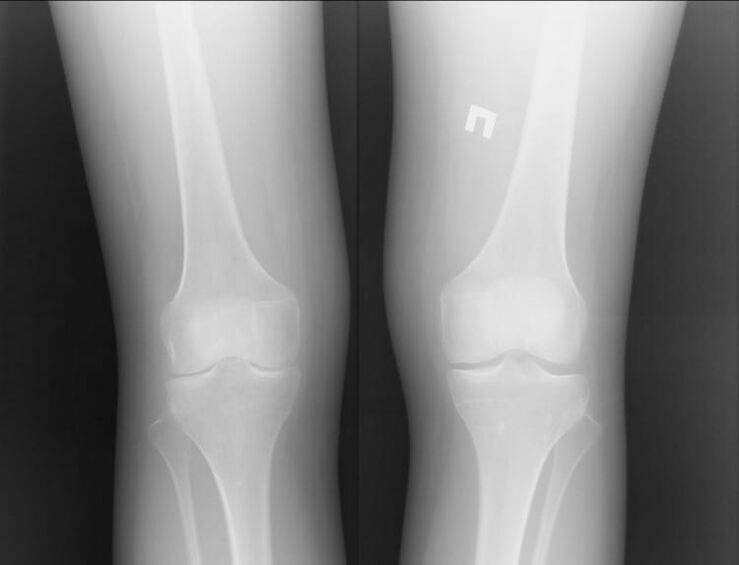

Arthrosis is a joint disease caused by cartilage problems.They begin to gradually break down and break, causing excruciating pain.It occurs in acute and long-term forms.It usually occurs in the morning or after strenuous physical activity.

Arthritis is largely a chronic disease.For a long time, you may not know you have this condition because it presents as temporary pain.However, it can be done quickly or slowly.If joint disease is not detected early, the disease can lead to disability.Symptoms of joint disease:

- Swelling around joints.With arthropathy, a different situation occurs: the joints swell only during the acute illness.The disease occurs with severe pain.

- There is a crunch and crispness in the joints.The crunching sound won't particularly bother the owner in the first place, but if left untreated, it can be heard by others.Feelings of vulnerability often occur after taking a shower or swimming in cold water.

- Painting hurts.This is especially true when the affected joints are under stress.For example, when climbing stairs.

Most often, arthrosis is caused by heavy loading or injury.The pain may worsen at night and last into the morning.

Of course, both diseases are serious, and it's hard to say which one is more serious.However, we can consider the example of knee joint problems.For arthritis, an inflammatory process, it can help patients.

Most often, this occurs due to other infections occurring in the body.If they are healed and inflammation of the joint is eliminated, knee arthritis will no longer bother you.

Arthropathy is a completely different story.This is a separate disease caused by problems with cartilage tissue.This often cannot be accomplished without surgical intervention.What follows is another lengthy recovery process.

Therefore, we can say that arthrosis is a more serious disease.However, arthritis can cause the first disease.Neither disease should be ignored.It is best to contact an expert immediately.